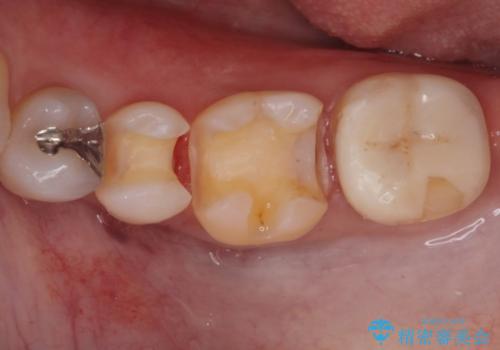

- 銀の詰め物が目立ので白くしたいとの事で来院。

とりあえず奥の二つから白くしたいとの事だったので

銀の詰め物を外し、e-maxインレーにしました。